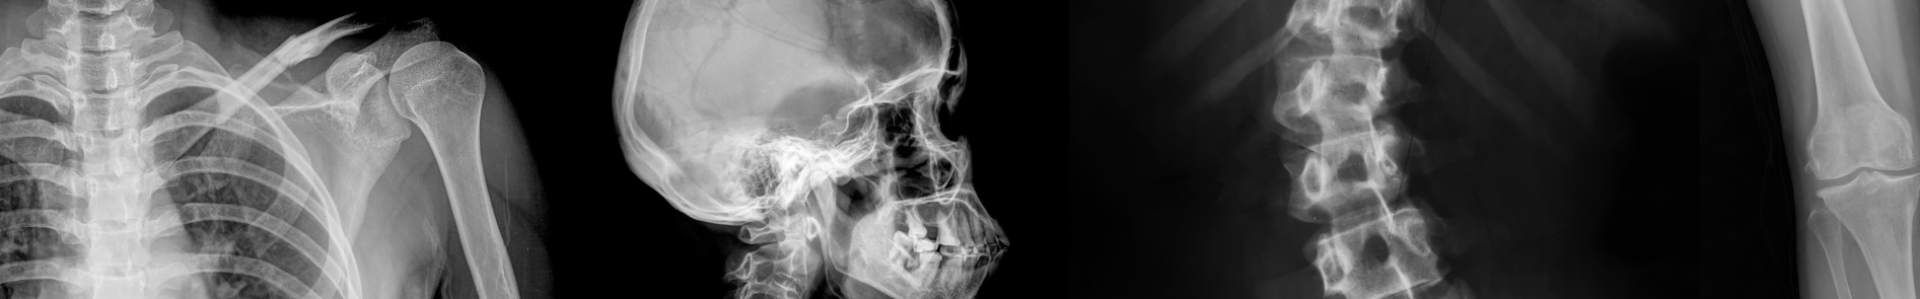

Learn advanced image interpretation skills covering the upper and lower limbs!

The Image Interpretation course is both an advanced course for medical teams communicating X-Rays and a guide that will give students with less experience an insight into the topics complexities.

This course will cover the fundamentals of image interpretation in a guided learning style and will then shift to an eLearning resource that covers the upper limb in one section and the lower limb in the other.

Throughout each eLearning resource the student will observe actual X-rays that have been pulled together alongside the stories that relate to them.

**This course does not cover the torso or head**